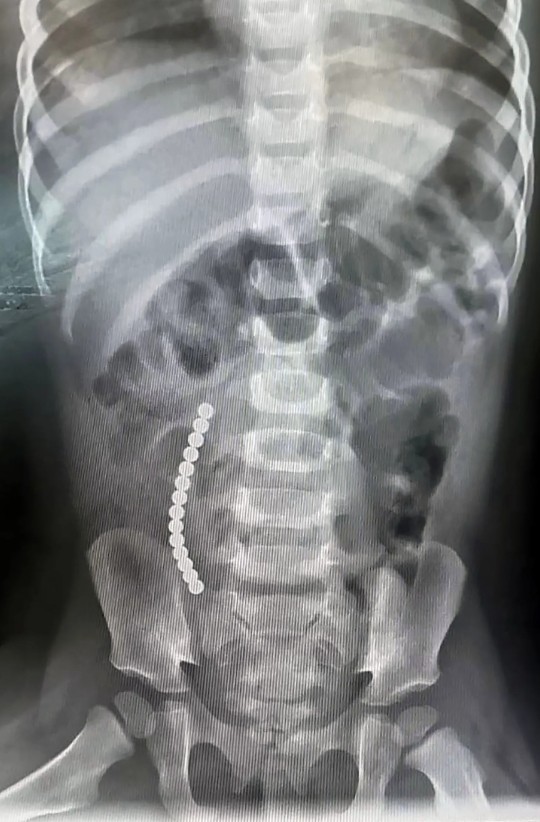

(给鲍比拍X光片)

“最后,我要求给他做CT,几个小时后,他们就安排他去做手术了,因为他们看到小磁珠已经在他的肠子里吸在一起了。”

(鲍比的肠子里,小磁珠吸在一起)

手术做了3个小时,医生把小磁珠取了出来,还不得不切掉了男孩的一段肠子。